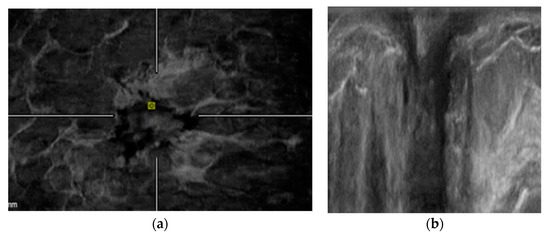

2.4. ABVS Interpretation